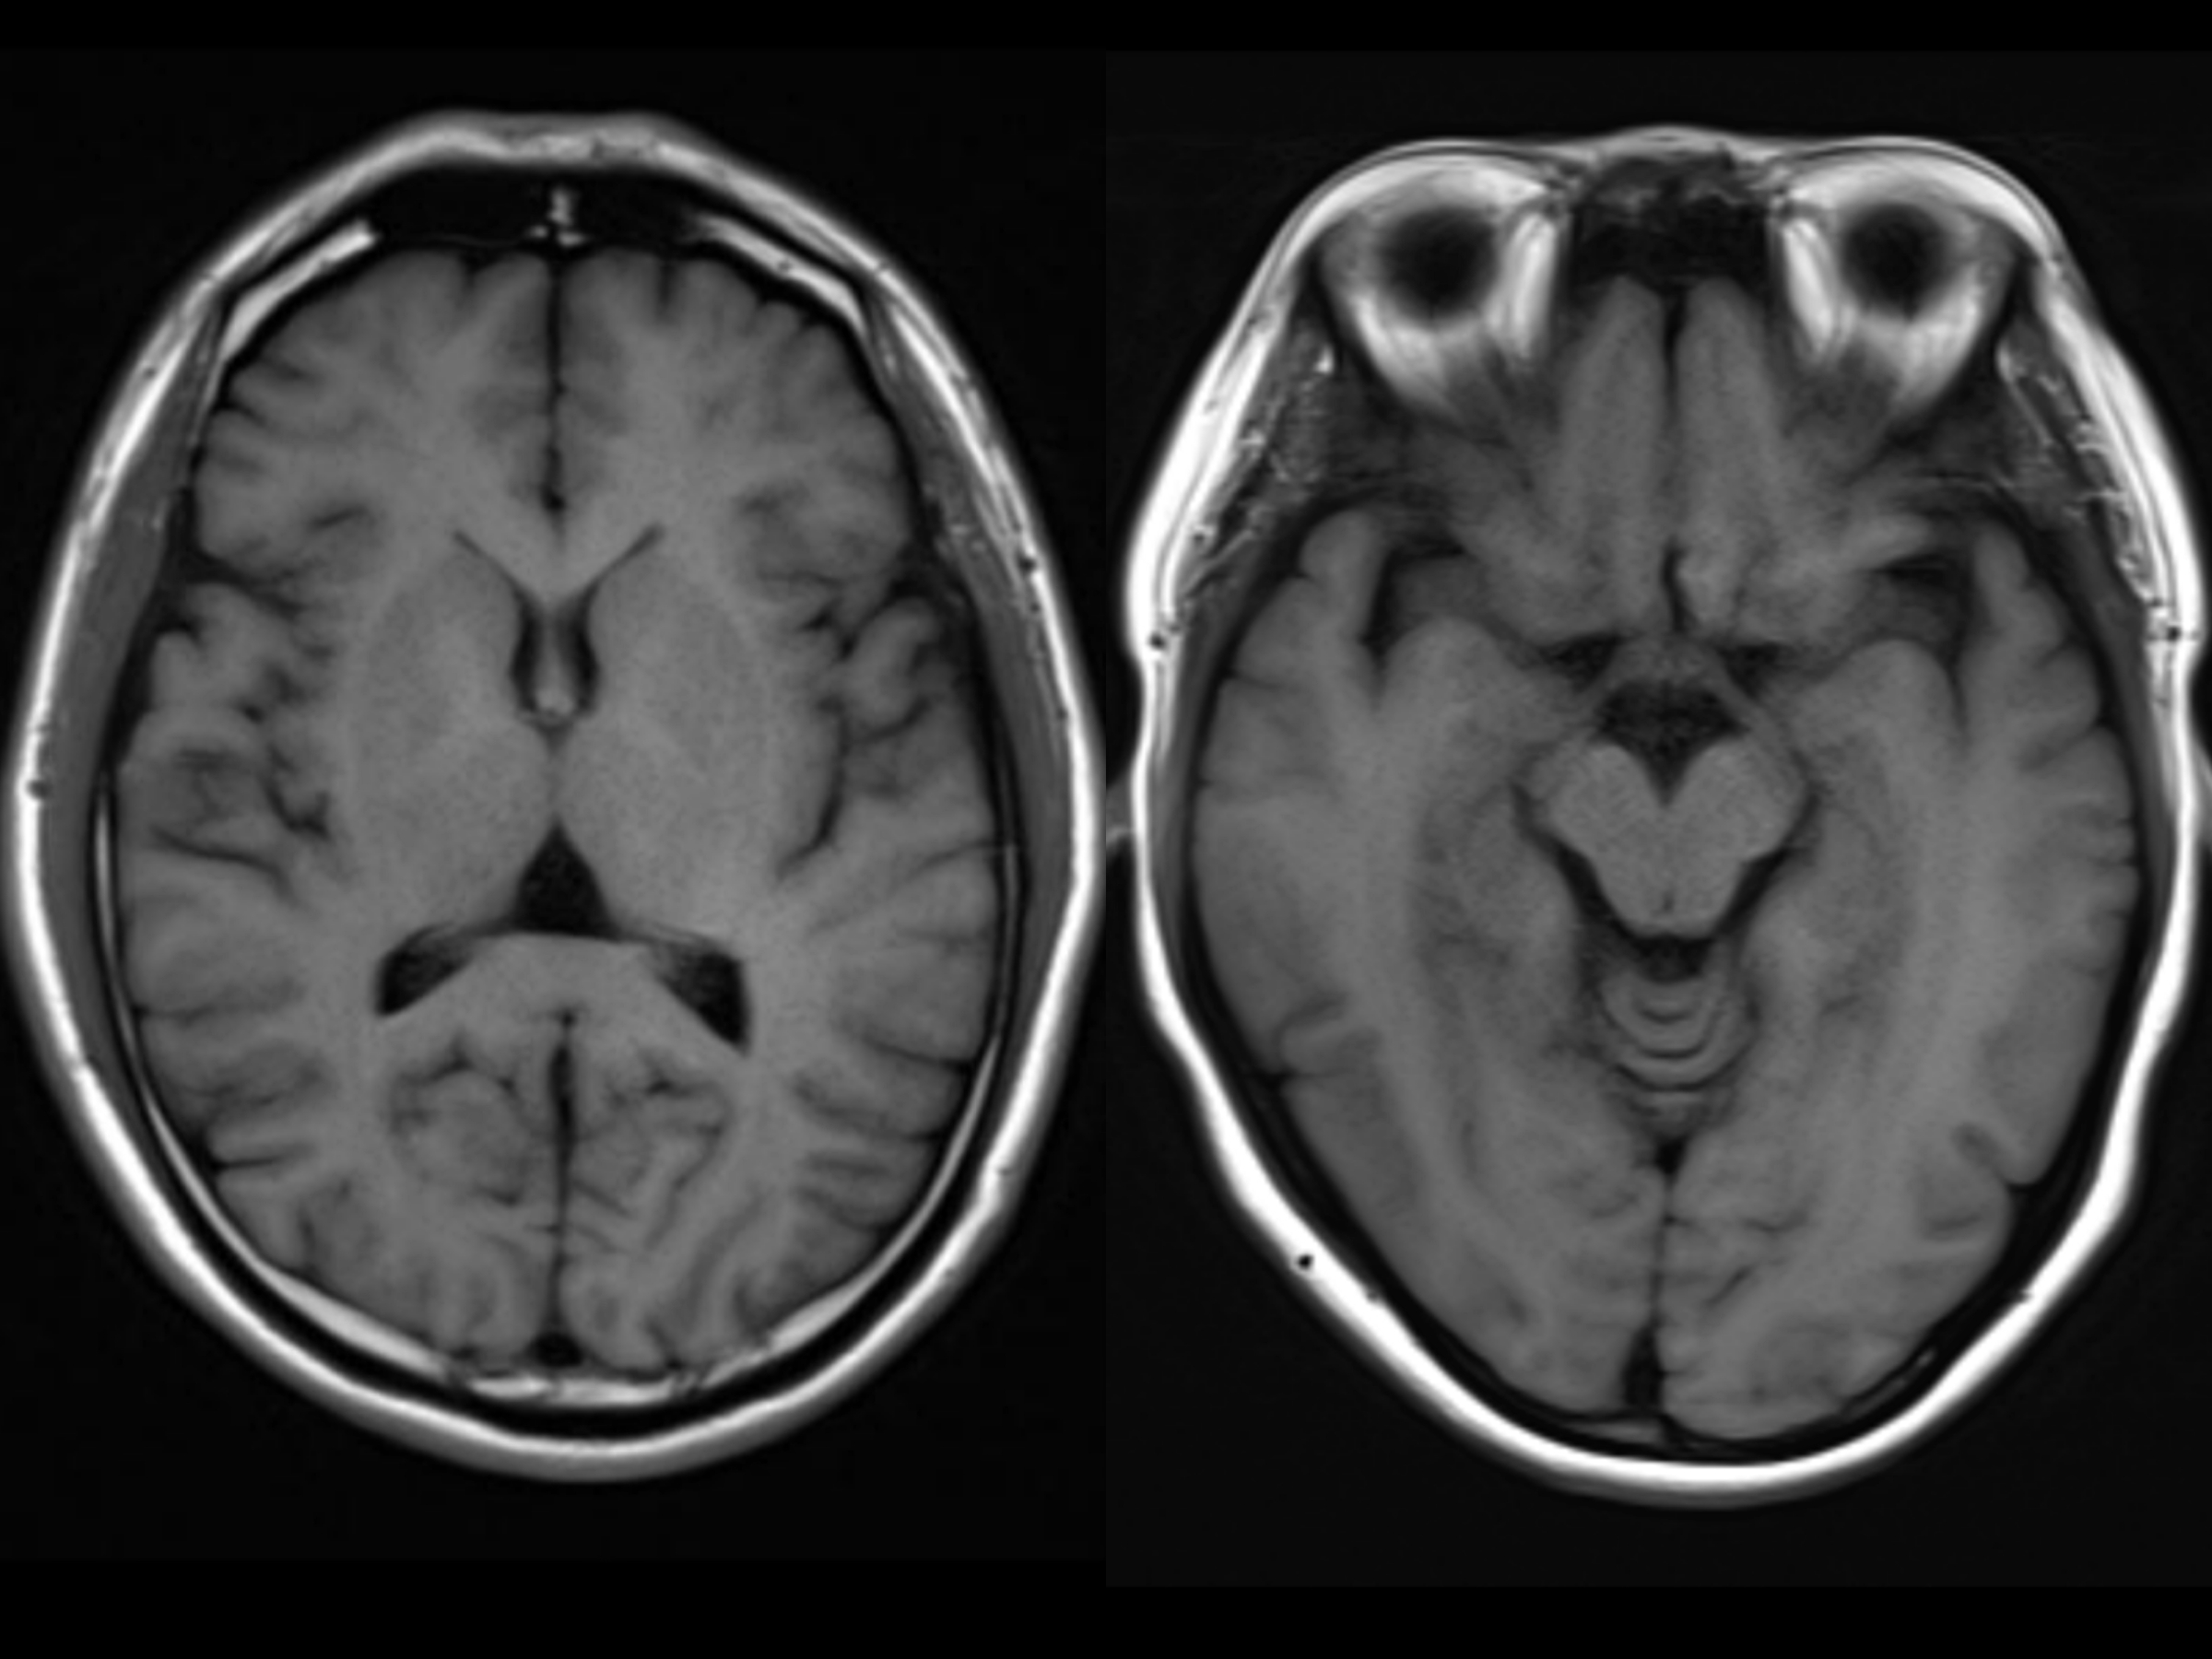

正常大脑和萎缩的大脑,ct和mri检查图像

图片尺寸2400x1800